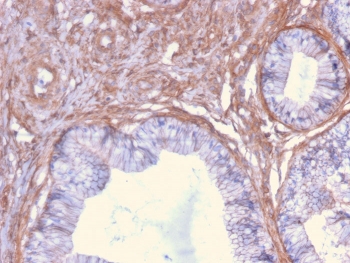

IHC staining of FFPE human cervix with Drebrin 1 antibody (clone DBN1/2879). HIER: boil tissue sections in pH 9 10mM Tris with 1mM EDTA for 10-20 min followed by cooling at RT for 20 min.